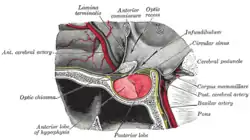

Mesal aspect of a brain sectioned in the median sagittal plane. The pituitary gland in position. Shown in sagittal section.

The pituitary gland in position. Shown in sagittal section. Cerebrum. Inferior view.Deep dissection